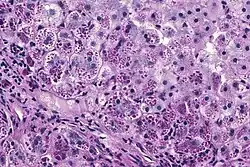

With A1AT deficiency, the pathogenesis of the lung disease is different from that of the liver disease, which is caused by the accumulation of abnormal A1AT proteins in the liver, resulting in liver damage.[9] As such, lung disease and liver disease of A1AT deficiency appear unrelated, and the presence of one does not appear to predict the presence of the other.[9] Between 10% and 15% of people with the PiZZ genotype will develop liver fibrosis or liver cirrhosis, because the A1AT is not secreted properly and therefore accumulates in the liver.[18] The mutant Z form of A1AT protein undergoes inefficient protein folding (a physical process where a protein chain achieves its final conformation). 85 percent of the mutant Z form are unable to be secreted and remain in the hepatocyte.[9] Nearly all liver disease caused by A1AT is due to the PiZZ genotype, although other genotypes involving different combinations of mutated alleles (compound heterozygotes) may also result in liver disease.[9] A liver biopsy in such cases will reveal PAS-positive, diastase-resistant inclusions within hepatocytes.[9] Unlike glycogen and other mucins which are diastase sensitive (i.e., diastase treatment disables PAS staining), A1AT deficient hepatocytes will stain with PAS even after diastase treatment - a state thus referred to as "diastase resistant". The accumulation of these inclusions or globules is the main cause of liver injury in A1AT deficiency. However, not all individuals with PiZZ genotype develop liver disease (incomplete penetrance), despite the presence of accumulated mutated protein in the liver.[9] Therefore, additional factors (environmental, genetic, etc.) likely influence whether liver disease develops.[9]